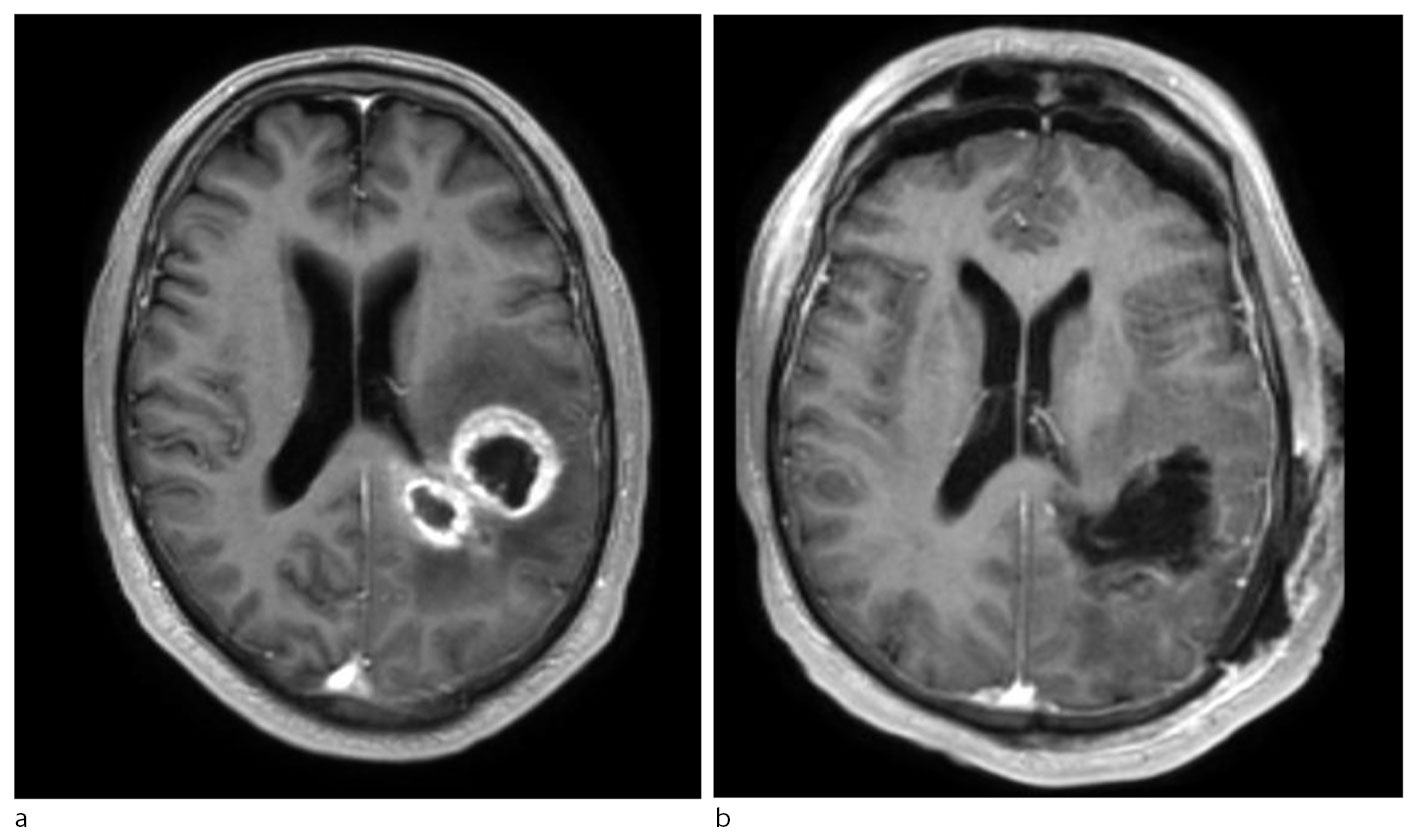

MR-undersøkelse av hodet er førstevalg ved radiologisk utredning av mistenkt glioblastom, og det er etablert regionale retningslinjer for slik diagnostikk. Glioblastomer fremstår som inhomogene lesjoner med uregelmessig avgrensning. De har typisk en kontrastoppladende periferi, sentral nekrose og perifokalt ødem (figur 1). Multifokale lesjoner kan også ses. Differensialdiagnoser er andre gliomer, metastaser, lymfomer, abscesser og demyeliniserende lesjoner (4).